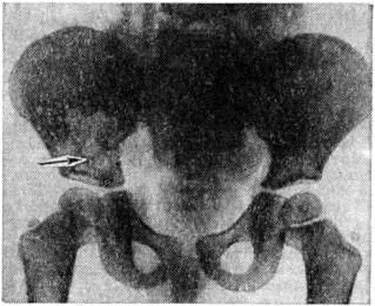

При Л.—С. б. наиболее часто поражаются плоские кости (череп, таз, лопатки). На обзорных рентгенограммах выявляются участки выраженного разрежения с чёткими границами, отдельные очаги достигают размеров 1 — 2 сантиметров Несколько небольших очагов могут сливаться между собой; в этом случае на рентгенограмме обнаруживаются крупные дефекты костной ткани, имеющие волнистые, иногда отчётливые фестончатые контуры (рисунок 2). Деструктивные очаги, разрушая прежде всего губчатое вещество кости, могут нарушать целость и коркового вещества; характерным для Л.—С. б. является отсутствие реакции надкостницы даже в тех случаях, когда при бурном течении процесса оказывается разрушенным и корковое вещество.

Рис. 2.

Рентгенограмма костей таза при болезни Леттерера — Сиве у ребёнка 3 лет: виден обширный очаг деструкции в правой подвздошной кости с волнистыми контурами (указано стрелкой).